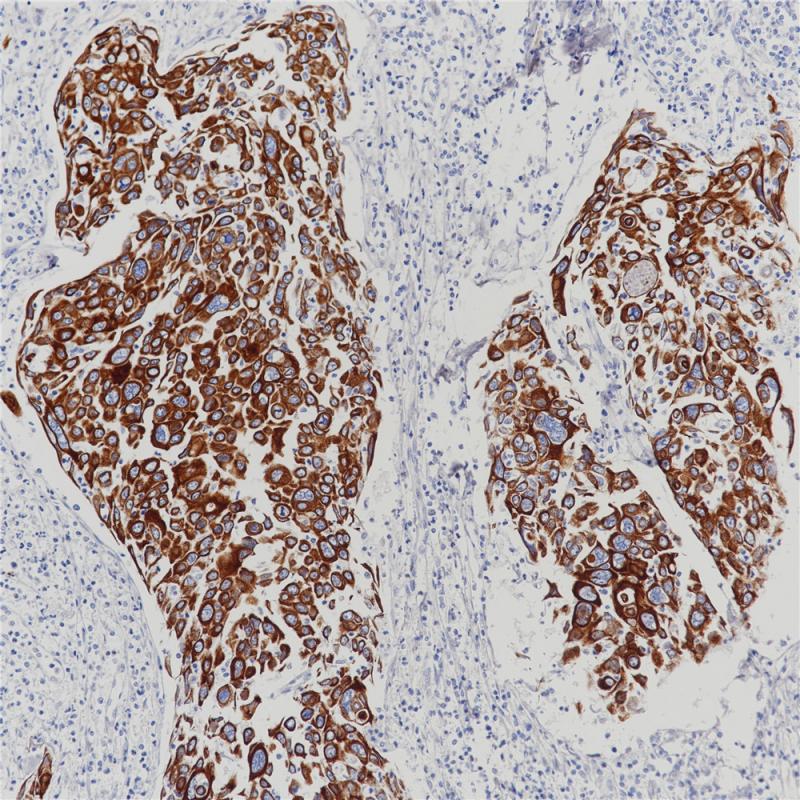

Topoisomerase II-α 重组兔单克隆抗体

阳性对照

宫颈癌

亚细胞定位

细胞核